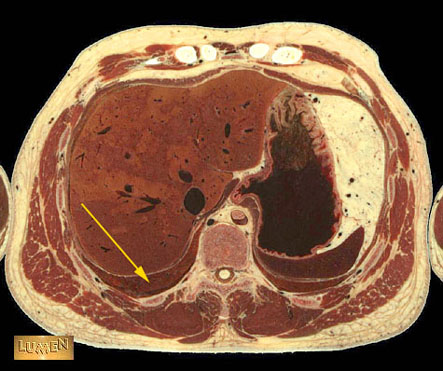

Question: Identify.

Lower lobe of right lung.